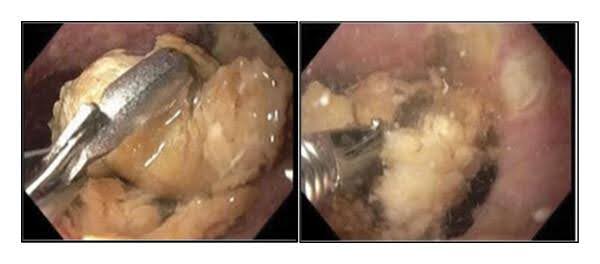

Befund der Magenspiegelung:

Abb. 3: Magenspiegelung1

Der 82-jähriger Patient litt unter einem Ösophagusbezoar, der sich im unteren Ösophagus befand. Es war nicht möglich gewesen, den Bezoar unter Zuhilfenahme der Raptor-Zange und der Talon-Greifzange zu entfernen. Es wurde eine Bronchoskopie durchgeführt, in der sich eitrige Sekrete und Speisereste in beiden Lungenflügeln zeigten. Aufgrund des hohen Patientenalters und den Komorbiditäten wurde zunächst kein chirurgischer Eingriff angedacht. Der nächste Behandlungsversuch beruhte auf der direkten Umspülung des Ösophagusbezoars mit kohlensäurehaltigen Flüssigkeiten (Coca-Cola), die mit Pankreasenzymen (KREON) infundiert wurden. Zu diesem Zeitpunkt war der Patient endotracheal intubiert, was das Risiko für eine tracheale Aspiration minimierte. Die Behandlung erfolgte für insgesamt 4 Tage (4 x tgl. (355 ml) Coca-Cola und 4 Kapseln KREON). Dies führte zu einer vollständigen Auflösung des Ösophagusbezoars. Leider blieb eine Ösophagitis mit zirkumferentiellen Ulzerationen zurück. Es zeigte sich zudem eine 5 cm große Hiatushernie. Durch eine Biopsie konnte eine eosinophile Ösophagitis ausgeschlossen werden.1